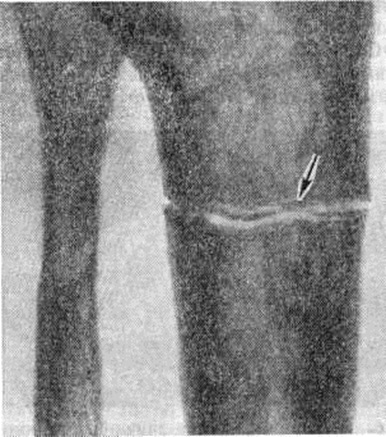

Перестраивающиеся длинные трубчатые кости постепенно искривляются, с выпуклой стороны нередко развиваются зоны патологической функциональной перестройки (смотри полный свод знаний: Лоозера зоны), на основе которых возникают характерные так называемый банановые переломы, проходящие поперечно к продольной оси кости и имеющие ровную, иногда изогнутую поверхность (рисунок 13).